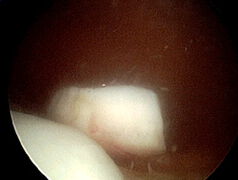

Meniskusschäden:

Meniskusschäden: Nur ein kleiner basisnaher Anteil der Menisken ist blutversorgt (und besitzt damit Heilungspotenz), deshalb müssen meistens zerstörte Meniskusanteile mittels kleiner Schneideinstrumentarien entfernt werden. Das Bein kann nach wenigen Tagen voll belastet werden, die Beweglichkeit wird nicht eingeschränkt. In seltenen Fällen (i.d.R. frischer, basisnaher Riss ohne Degeneration) kann der Meniskus durch Naht erhalten werden. Die Entlastungsdauer zur Heilung beträgt ca. 6 Wochen, je nach Lokalisation der Naht muß die Kniegelenksbeweglichkeit ggf. mit einer Schiene eingeschränkt werden.